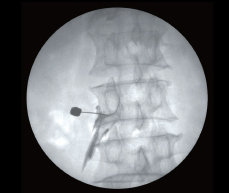

Мощный генератор и вращающийся анод рентгеновской трубки обеспечивает готовность к продолжительным манипуляциям под рентгеновским контролем. Ангиографический пакет и широкий диапазон импульсных режимов позволяет достичь максимальной безопасности в диагностике. Большое свободное пространство С-дуги улучшает возможность позиционирования, снижая необходимость лишних действий оператора.

Область применения:

- общая рентгенология;

- ортопедия;

- травматология;

- гинекология;

- урология;

- нейрология;

- сосудистая хирургия.